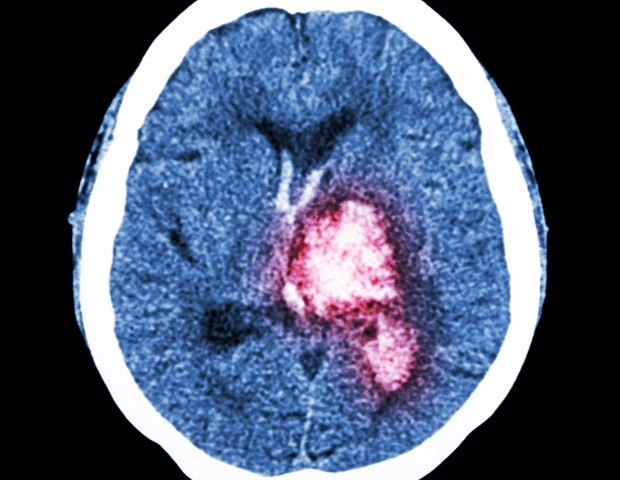

למולקולות המחסום החיסוניות תפקיד מכריע בשמירה על איזון מערכת החיסון ומניעת התקפה על תאי הגוף עצמו. תאים סרטניים יכולים להשתמש

בתוך גידולים בגוף האדם, ישנם תאי חיסון (מקרופאגים) המסוגלים להילחם בסרטן, אך הם לא הצליחו לבצע את תפקידם כראוי עקב